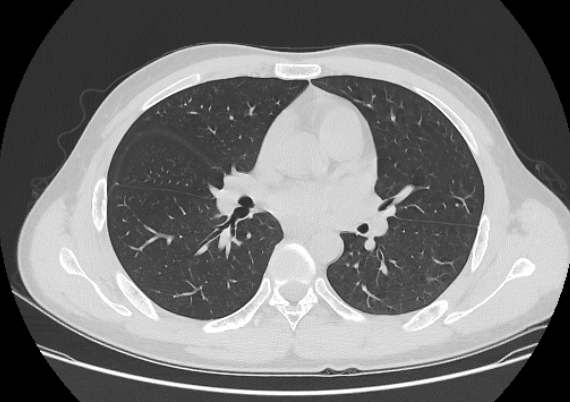

CT Lung

CT Lung CTA

Analytics CT Lung

CT Lung MRI Brain